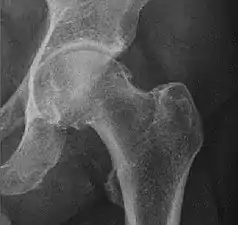

X-ray of the hips of a 40-year-old female, with dysplasia of her right hip.

In the adult hip there are important landmarks to be recognized on plain film radiographs:[3]